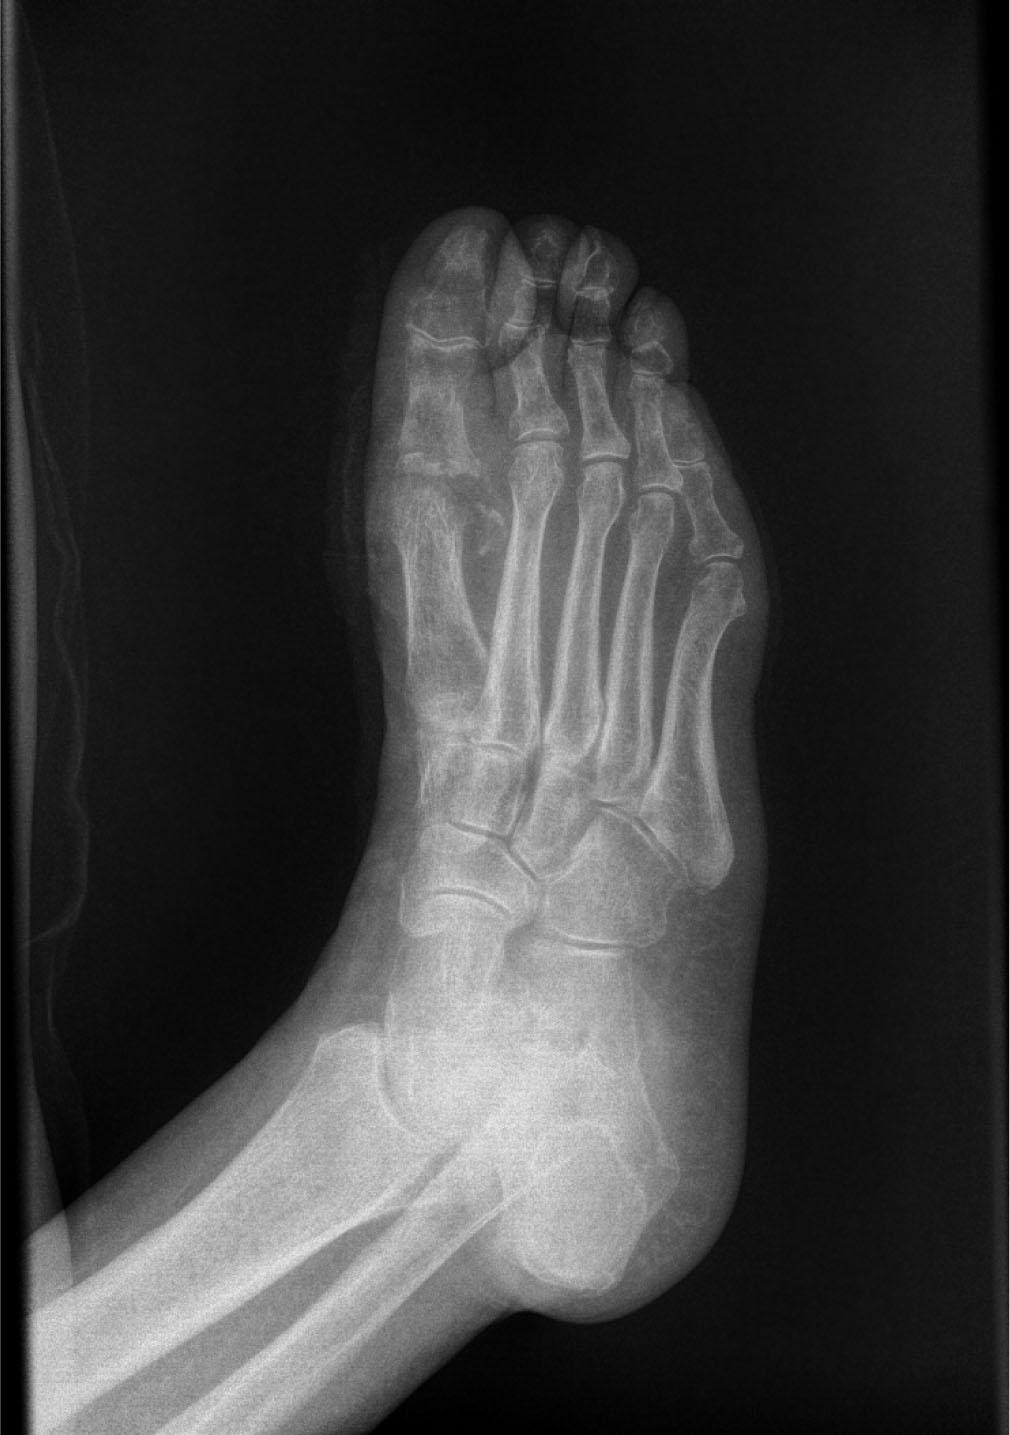

A 73-year-old female patient was first admitted in November 2023. to the Department of Baromedicine at the Zemun Clinical Hospital Center due to a non-healing wound on her right foot. The ulcer was located on the inside of the right foot in the projection of the head of the first metatarsal bone, 6 cm in diameter, with signs of infection and necrotic content (Figure 1). The patient gives information that the change occurred about a month before hospitalization and that it was a minor wound, probably the result of blisters. Until admission, she was treated in a regional health institution with bandages and antibiotic therapy. The skin of both feet is trophically altered, pedal pulsations are not palpable. The patient has been diabetic for 18 years, on combined insulin and oral therapy. She is being treated for hypertension, hyperlipoproteinemia and psoriasis as well. A swab of the wound was taken upon admission. After an examination by a cardiologist and otorhinolaryngologist and an x-ray of the heart and lungs, the patient was treated with HBO according to the regular protocol included. HBOT was conducted in a one-piece chamber that accommodates only a single patient, in which he lies only in his cotton underwear, under a pressure of 2 ATA for 60 minutes once a day. During treatment, the pressure is raised by the first 15 minutes at a rate of 0.3 ATA per minute, the next half hour, the patient breathes 100 % O2 under constant pressure from 2 ATA, and last 15 minutes gradual decompression is also made at 0.3 ATA per minute. A total of 20 HBO therapies were conducted. Immediately upon admission, empiric antibiotic therapy was included, which was corrected in accordance with the results of the wound swab, from which Pseudomonas aeruginosa was isolated, and the antibiogram. Wound care with hydrogen and povidone-iodine solution were performed daily, with occasional debridement of necrotic tissue and drainage of the contents. During hospitalization, leukocytes ranged from 9.4-7.1 (10*9/L), CRP 74.7-28.6 (mg/L). At the end of the treatment, the patient was discharged in good general condition with local findings improving, without signs of infection and with the appearance of clear granulation tissue in the area of the ulcer, with a recommendation to continue treatment and bandages in the regional health institution. Two months after her discharge, the patient comes for a follow-up examination, stating that she regularly received bandaging and antibiotic treatment from the attending physician through the Community health center's home healthcare service. The local findings show a wound that is almost completely filled with granulation tissue, with macerated edges, apparently without infection (Figure 2). By pressing in the region of the root of the thumb plantar path of the wound, a larger amount of purulent content is obtained. The patient was hospitalized at the end of February 2024. in the Baromedicine Service again and treated with hyperbaric oxygen therapy according to the same protocol as the previous time. A total of 15 HBOTs were conducted. A swab of the wound was taken, from which Pseudomonas aeruginosa was isolated again, and it was treated with antibiotic therapy based on the results of the swab and the antibiogram, the wound was regularly bandaged with curettage of the place where the purulent content was obtained and its drainage. X-ray of the foot did not show the presence of gas in the soft tissue structures of the foot or signs of bone infection (Image 1,2). During the second hospitalization, leukocytes ranged from 8.1-6.4 (10*9/L), CRP 8.1-10.1 (mg/L). At the end of the therapy, the patient was discharged in a good condition, with a significant improvement in the local findings and minimal slightly cloudy secretion (Figure 3). Further control and follow-up by the attending surgeon was advised. Six months after the last cycle of HBOT, the wound has completely healed (Figure 4).

Lateral X-ray image of the right foot